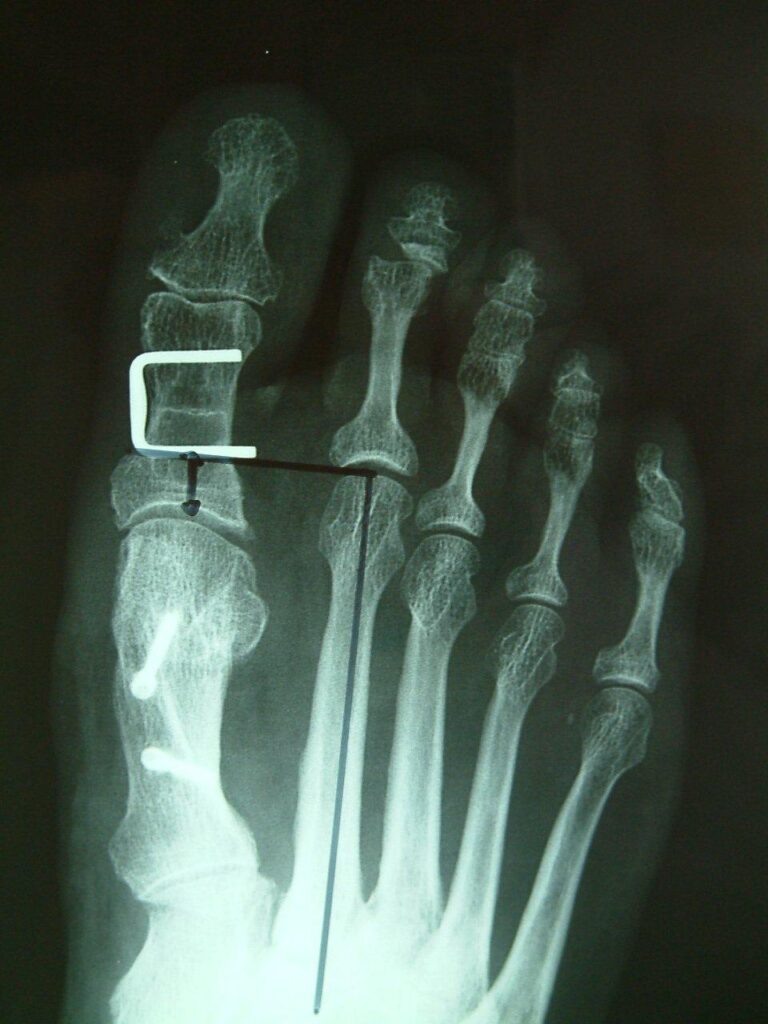

The common operative treatments of bunions involve bony correction through cuts of bone and fixation with screws as well as release of tight tissue structures and tightening of loose ones. Many operations for bunions have been tried over the years with varying levels of success. Techniques often vary from patient to patient depending on anatomy and bony alignment as well as soft tissue laxity.

More modern techniques involved smaller incisions and the use of specialised burrs and screws to minimise tissue damage. Several options for the different presentations of bunions exist and a discussion of the right techniques for your condition is required.

The metalwork used for fixing the bones may occasionally need to be removed. Recovery times and swelling vary from patient to patient.